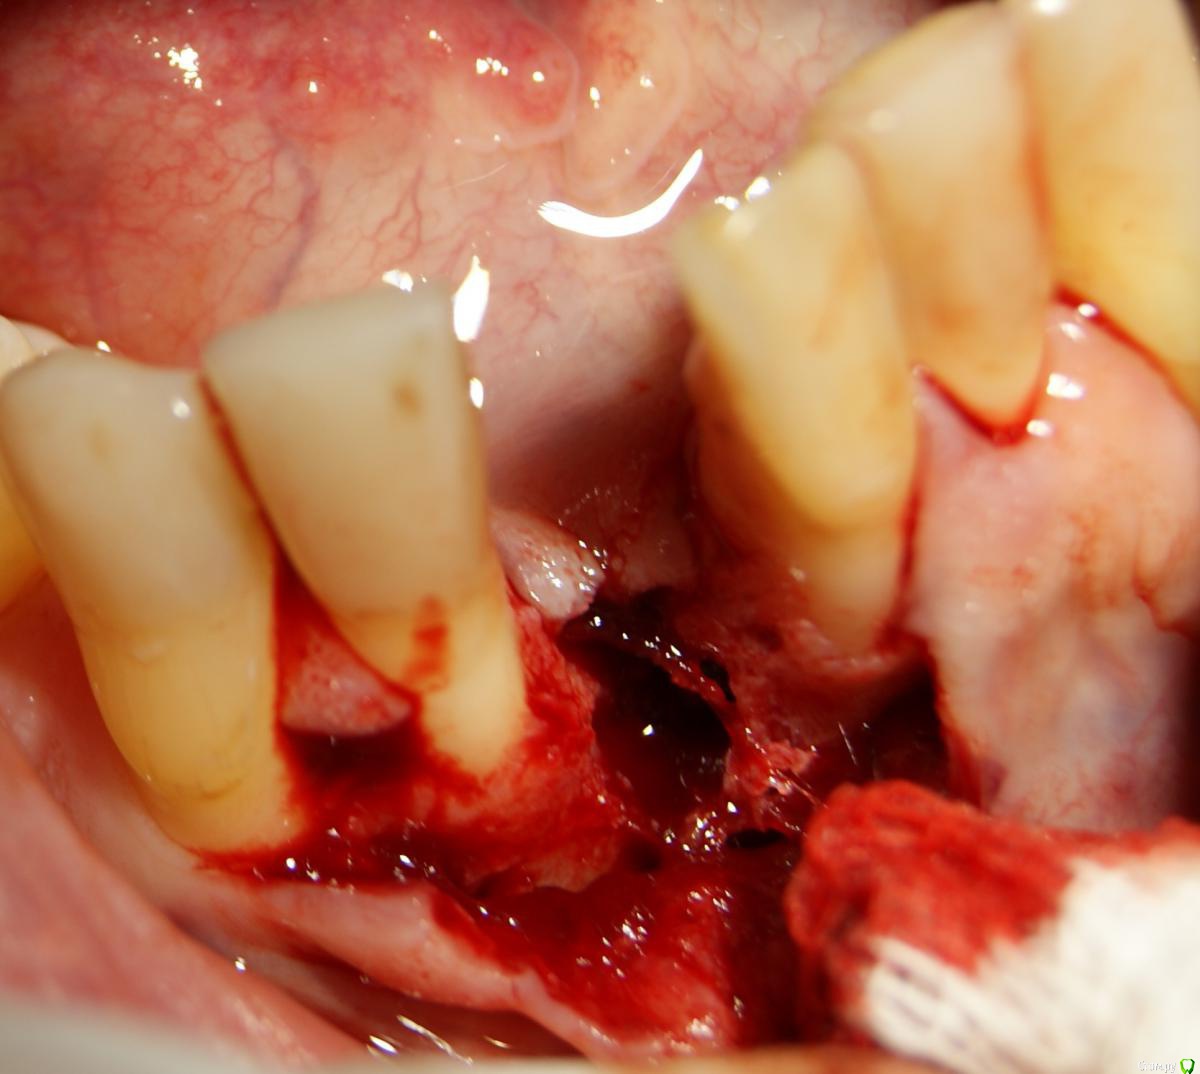

Jurai Опубликовано 25 декабря, 2016 Поделиться Опубликовано 25 декабря, 2016 *Предупреждение: фото на "мыльницу", не все этапы удались, но я работаю над этим) Вот пациент. Приятнейший, во всех отношениях, с негативным отношениям к мостовидным конструкциям. Полтора года лечил 41з по поводу периодонтита: толку не вышло. Удалил у широко известного многим стоматологам, особенно выпускам последних годов, доктора с ученой степенью. После удаления 4 месяца, по КТ область вполне достойно выглядит. Вот с чем пришел, обычное дело, все прилично: Раскрываю, а там между тонкими кортикалками мягко и упруго - резидуальная, фото нет. Открываю сильнее чем обычно, с расстройства не особо удачно. Кюретаж : Вид после, ушла вестибулярная кортикальная вместе с кистой: Сверлим 2,0, позиционердля рентген-контроля Имплантат ADIN UNP2,75Х11,5мм Ауто, джейсон коллагенфлис (что было под рукой) Швы. Контроль, перещелкивать не стали. В общем, понравился имплантат, для себя пометку кюретажить тщательнее, не надеяться, что организм все переварит. 1 9 Ссылка на комментарий